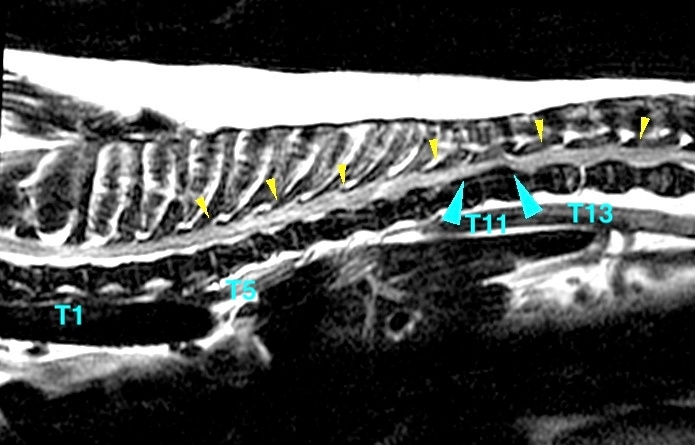

<症例情報> ボーダーコリー未去勢雄 5歳 18kg 主訴:数週間前からどこかを痛がっており、数日前からふらつくようになったとのことで来院。身体検査で…